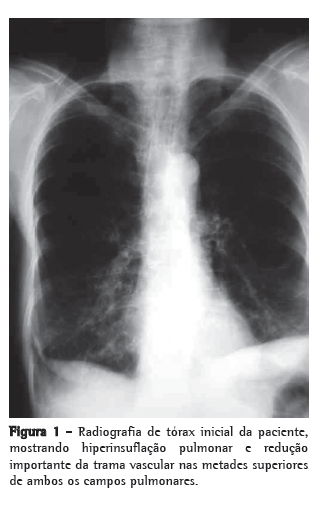

Encontrava-se em uso de levotiroxina, calcitriol e prednisona 15 mg/dia, mas já havia feito uso de metotrexato previamente. Ao exame físico, apresentava-se emagrecida (30 kg de peso e índice de massa corpórea de 14 kg/m2), sem linfonodomegalia cervical ou supraclavicular e sem baqueteamento digital. A ausculta pulmonar revelou apenas murmúrio vesicular reduzido difusamente. A radiografia de tórax no início do quadro, há 4 anos, mostrava hiperinsuflação pulmonar e redução importante da trama vascular nas metades superiores de ambos os campos pulmonares (Figura 1), e a TCAR realizada revelara enfisema parasseptal, cavidades e destruição do parênquima com predomínio nos lobos superiores (Figura 2). A gasometria arterial e o teste tuberculínico não revelaram anormalidades. A espirometria mostrou distúrbio ventilatório obstrutivo incipiente, sendo iniciado tratamento com formoterol. No último ano, com a piora dos sintomas, a paciente foi submetida à nova TCAR, que mostrou piora do padrão radiológico (Figura 3). A baciloscopia direta do escarro foi negativa para BAAR. O método Gomori-Grocott com prata metenamina evidenciou formas leveduriformes intracelulares, e as culturas das amostras de escarro e do lavado broncoalveolar em ágar dextrose Sabouraud revelaram a presença de Histoplasma capsulatum. Foi iniciado tratamento com itraconazol, 200 mg/dia.(8) A paciente encontra-se em acompanhamento ambulatorial com melhora sintomática e aumento de peso.

O aspecto radiológico da lesão inicial ­caracteriza-se por infiltrado inflamatório intersticial localizado, adjacente às bolhas enfisematosas, e frequentemente acometendo os segmentos apicais e apicoposteriores dos lobos superiores.(2,5,6,10) É comum que haja espessamento das paredes das bolhas com subsequente necrose e aumento da fibrose levando à perda de volume pulmonar. Esse processo contínuo culmina na formação de cavidades grandes e persistentes que podem ocupar o espaço de todo um lobo.(10) A disseminação de material fúngico para porções pulmonares pendentes pode ser o mecanismo de desenvolvimento de fibrose intersticial nos lobos inferiores por criação de novos focos inflamatórios.(4,10) Adenopatias mediastinais não são observadas nessa forma clínica, o que diferencia a HPCC de outras doenças granulomatosas, como a sarcoidose.(4,14)